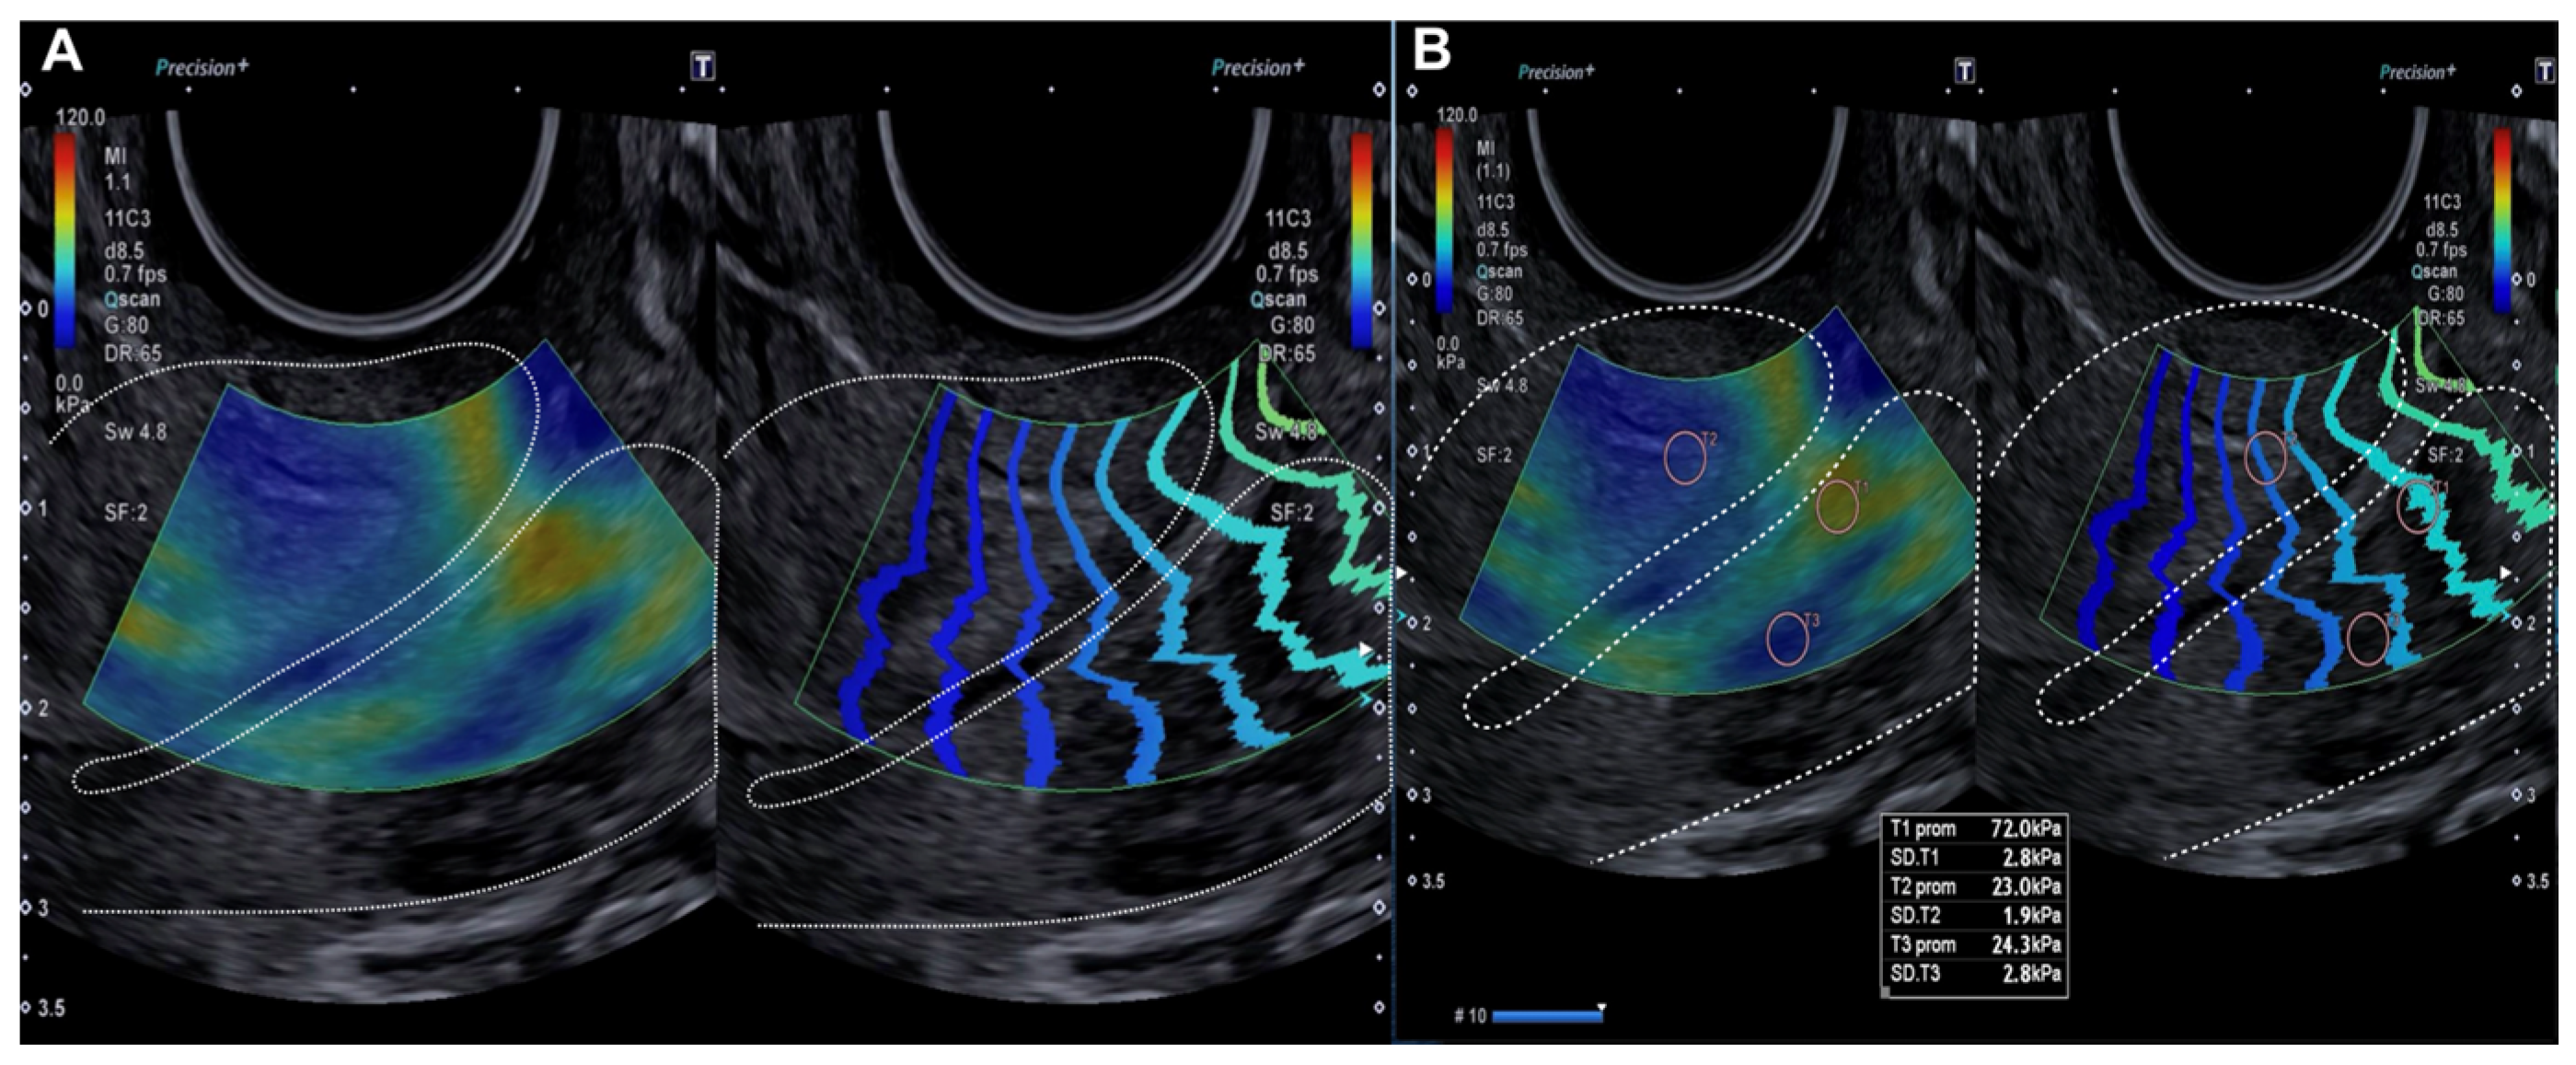

2.2.2. Evaluation Using SonoElastoColposcopy

- Sainz, J.A.; Castro, L.; Romo, J.M.; Holgado, A.; Fernández-Palacín, A.; García-Mejido, J.A. Evaluation of Pre-Malignant Lesions of the Uterine Cervix by Shear Wave Elastography: A New Diagnostic Tool. Ultrasound Med. Biol. 2021, 47, 3275–3282. [Google Scholar]

- Dudea-Simon, M.; Dudea, S.M.; Ciortea, R.; Malutan, A.; Mihu, D. Elastography of the uterine cervix in gynecology: Normal appearance, cervical intraepithelial neoplasia and cancer. A systematic review. Med. Ultrason. 2021, 23, 74–82. [Google Scholar] [CrossRef]

- Liu, C.; Li, T.T.; Hu, Z.; Li, Y.; Cheng, X.; Zhu, Y.; Lu, M. Transvaginal Real-Time Shear Wave Elastography in the Diagnosis of Cervical Disease. J. Ultrasound Med. 2019, 38, 3173–3181. [Google Scholar] [CrossRef]